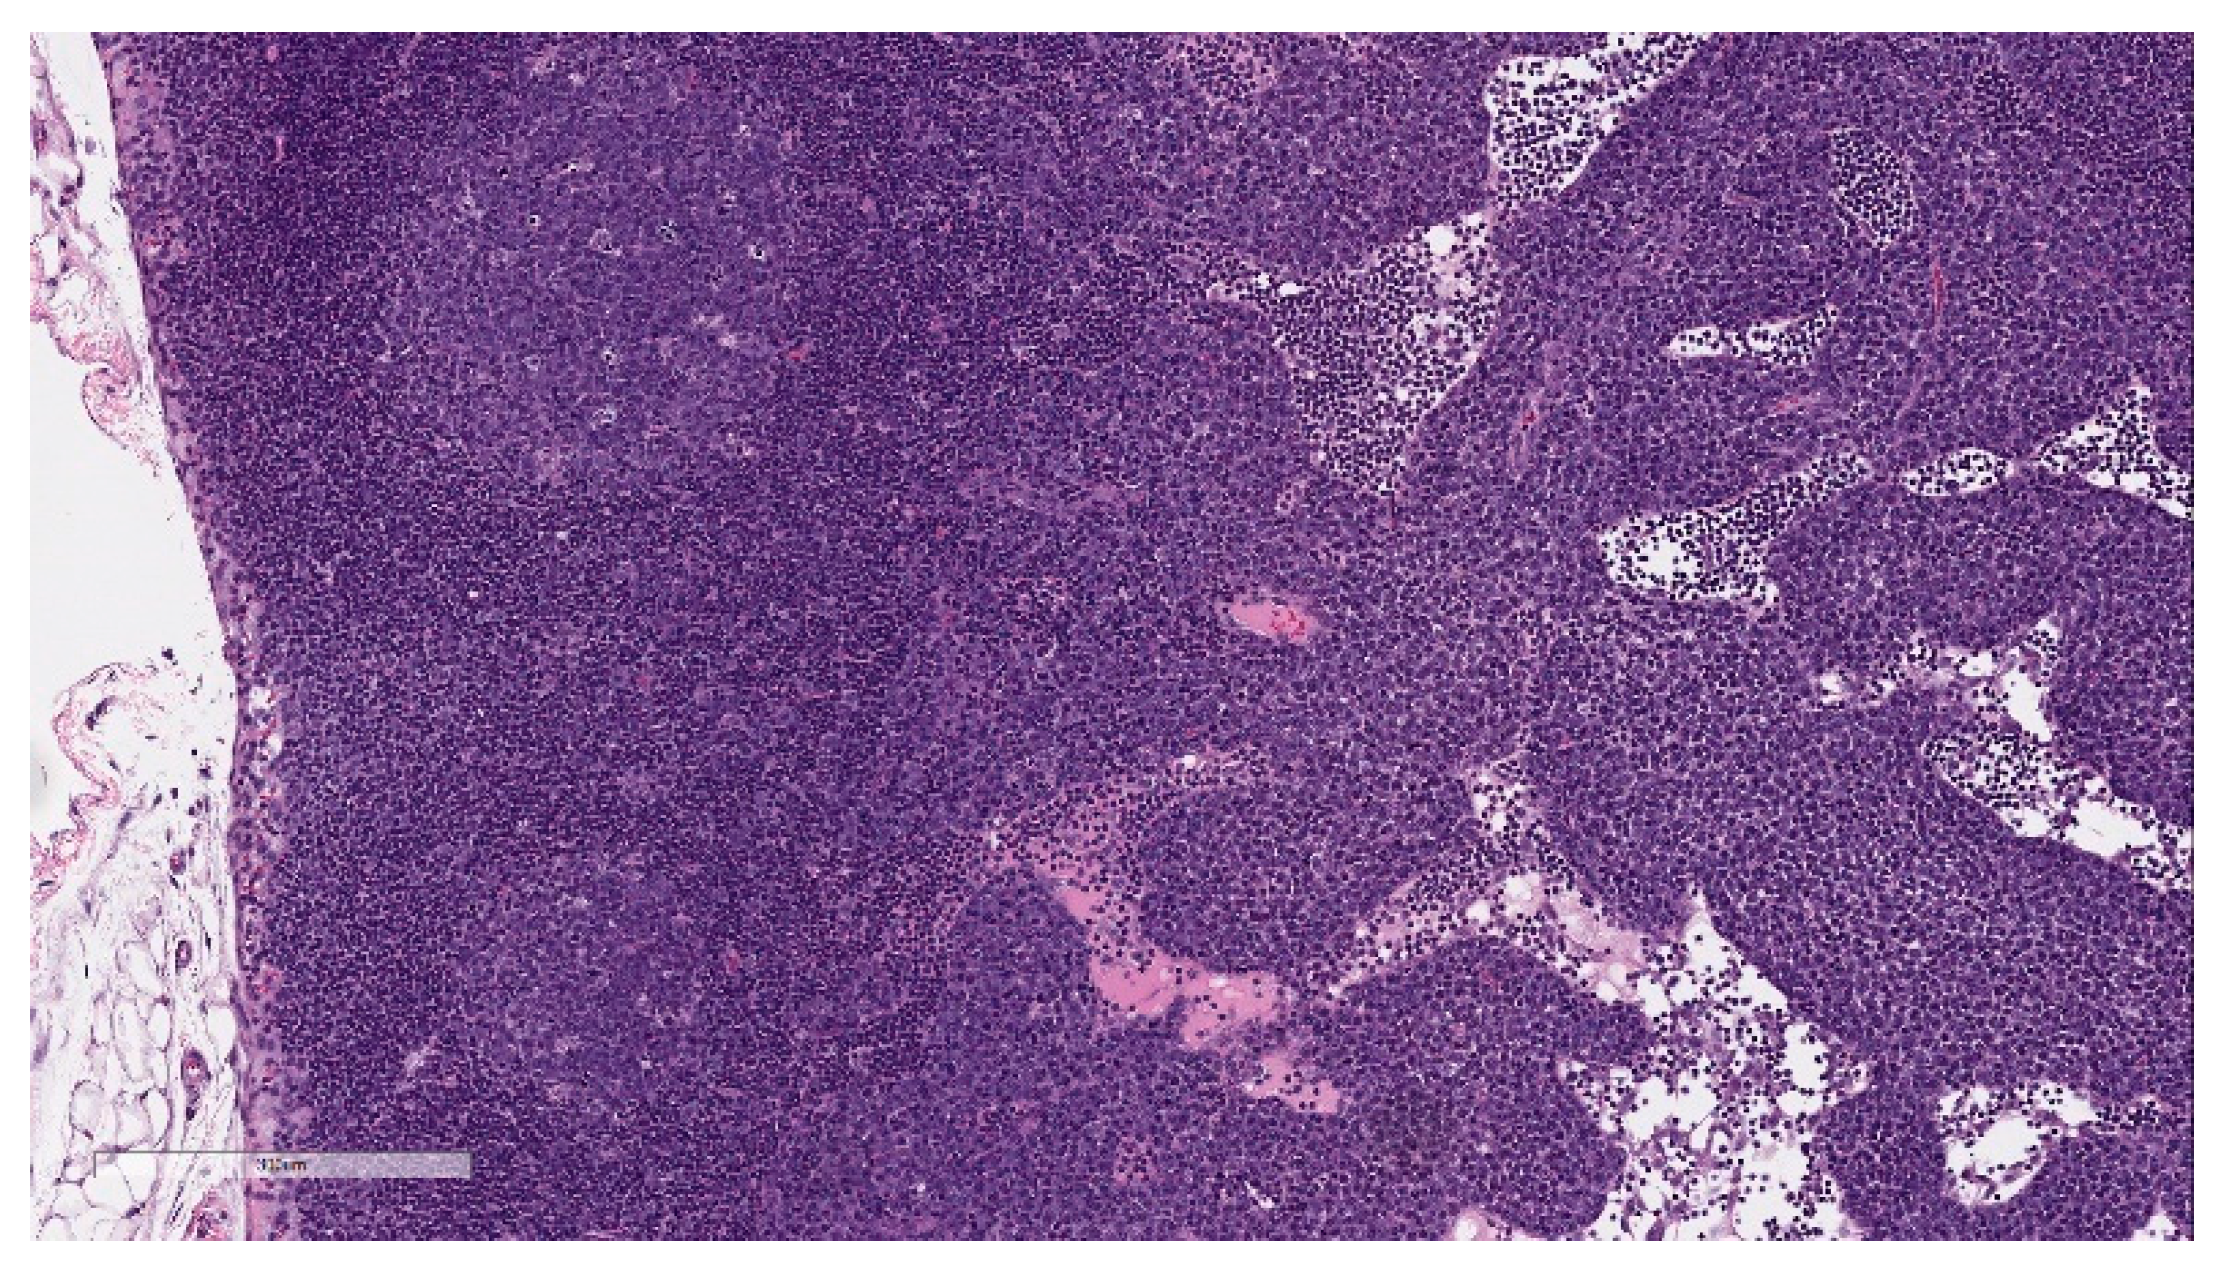

Microscopic findings in enlarged draining and inguinal lymph nodes correlated with increased germinal center cellularity, similar to the spleen, as well as increased numbers of immature plasma cells (plasmablasts) (Figure 8). At the end of the 3-week recovery phase, the increased cellularity of germinal centers was partially recovered, and the immature plasma cells were replaced by mature plasma cells.